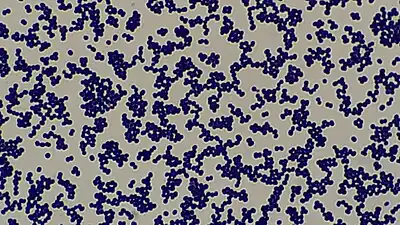

| SEM micrograph of S. aureus colonies; the grape-like clustering is common to Staphylococcus species. | |

The generic name Staphylococcus is derived from the Greek word "staphyle", meaning bunch of grapes, and "kokkos", meaning granule. [39]

The bacteria, when seen under a microscope, appear like a branch of grapes[40]